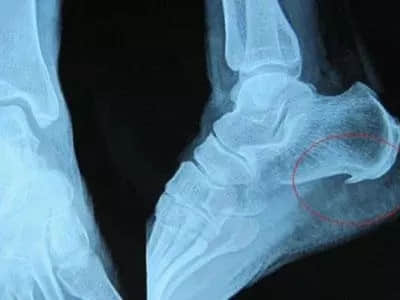

“骨刺”也叫骨质增生、骨赘,是关节因种种原因造成软骨的磨损、破坏,并促成骨头本身的修补、硬化与增生。骨刺像脸会长皱纹、人体会衰老一样,是一种自然的老化现象,并不是疾病。

骨刺的形状,其实并不像它的名字中的“刺”一样,更多的是光滑的、鳞片状的,不会扎到肉里。而且绝大多数的骨刺没有什么症状,只是悄悄的在生长、维持机体的平衡。